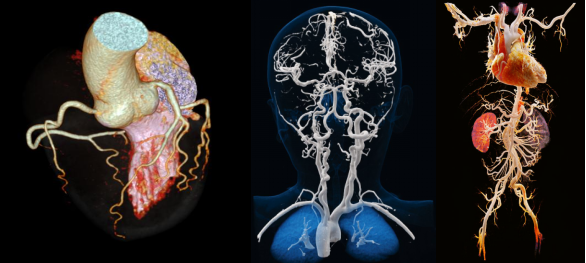

大范围血管成像:一站式完成多部位血管筛查依托极速扫描优势,1秒钟可完成胸腹大血管、头颈心一站式筛查,在胸痛三联征、心脏+腹部血管+下肢血管联合成像等复杂检查中应用广泛,实现多血管病变的一次性精准诊断。

全器官灌注检查:形态+功能双重评估,助力精准诊疗动态采集覆盖范围高达80cm,可实现神经、肝脏22cm大范围全器官灌注成像,同步获取器官形态学与功能学信息,辐射剂量更低,为肿瘤良恶性鉴别、缺血性疾病评估提供全面依据。